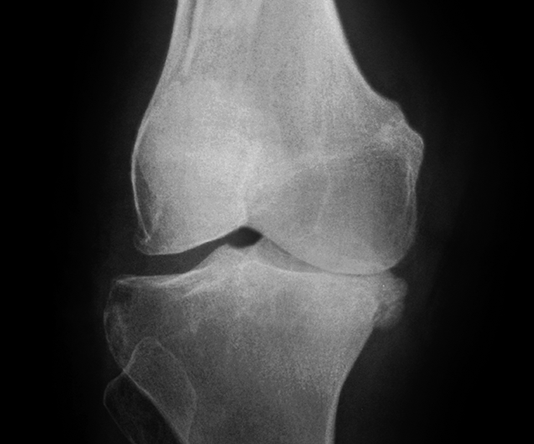

Hình ảnh so sánh giữa khớp bình thường và khớp bị thoái hóa khớp gối

Để phân biệt các giai đoạn của bệnh thoái hóa khớp gối, cần dựa vào phim X- quang theo tiêu chuẩn chẩn đoán thoái hoá khớp của Kellgren và Lawrence như sau:

Hình ảnh của khớp gối trên phim X-quang: Khe khớp hẹp nhẹ, có gai xương nhỏ.

Giai đoạn 2 vẫn được xem là giai đoạn tiến triển nhẹ, xem trên phim X-quang có thể thấy kích thước bề mặt sụn khớp vẫn chưa có sự thay đổi nhiều. Bao hoạt dịch khớp vẫn hoạt động bình thường, cung cấp đủ dịch khớp để nuôi dưỡng sụn và bôi trơn ổ khớp, giúp các đầu xương hoạt động được trơn tru. Mặc dù vậy, bệnh nhân vẫn có thể xuất hiện một số triệu chứng như đau mỏi ở khớp gối sau khi vận động nhiều hoặc khi làm việc quá sức, làm việc sai tư thế; cứng khớp khi trời lạnh hoặc do ít vận động khớp.